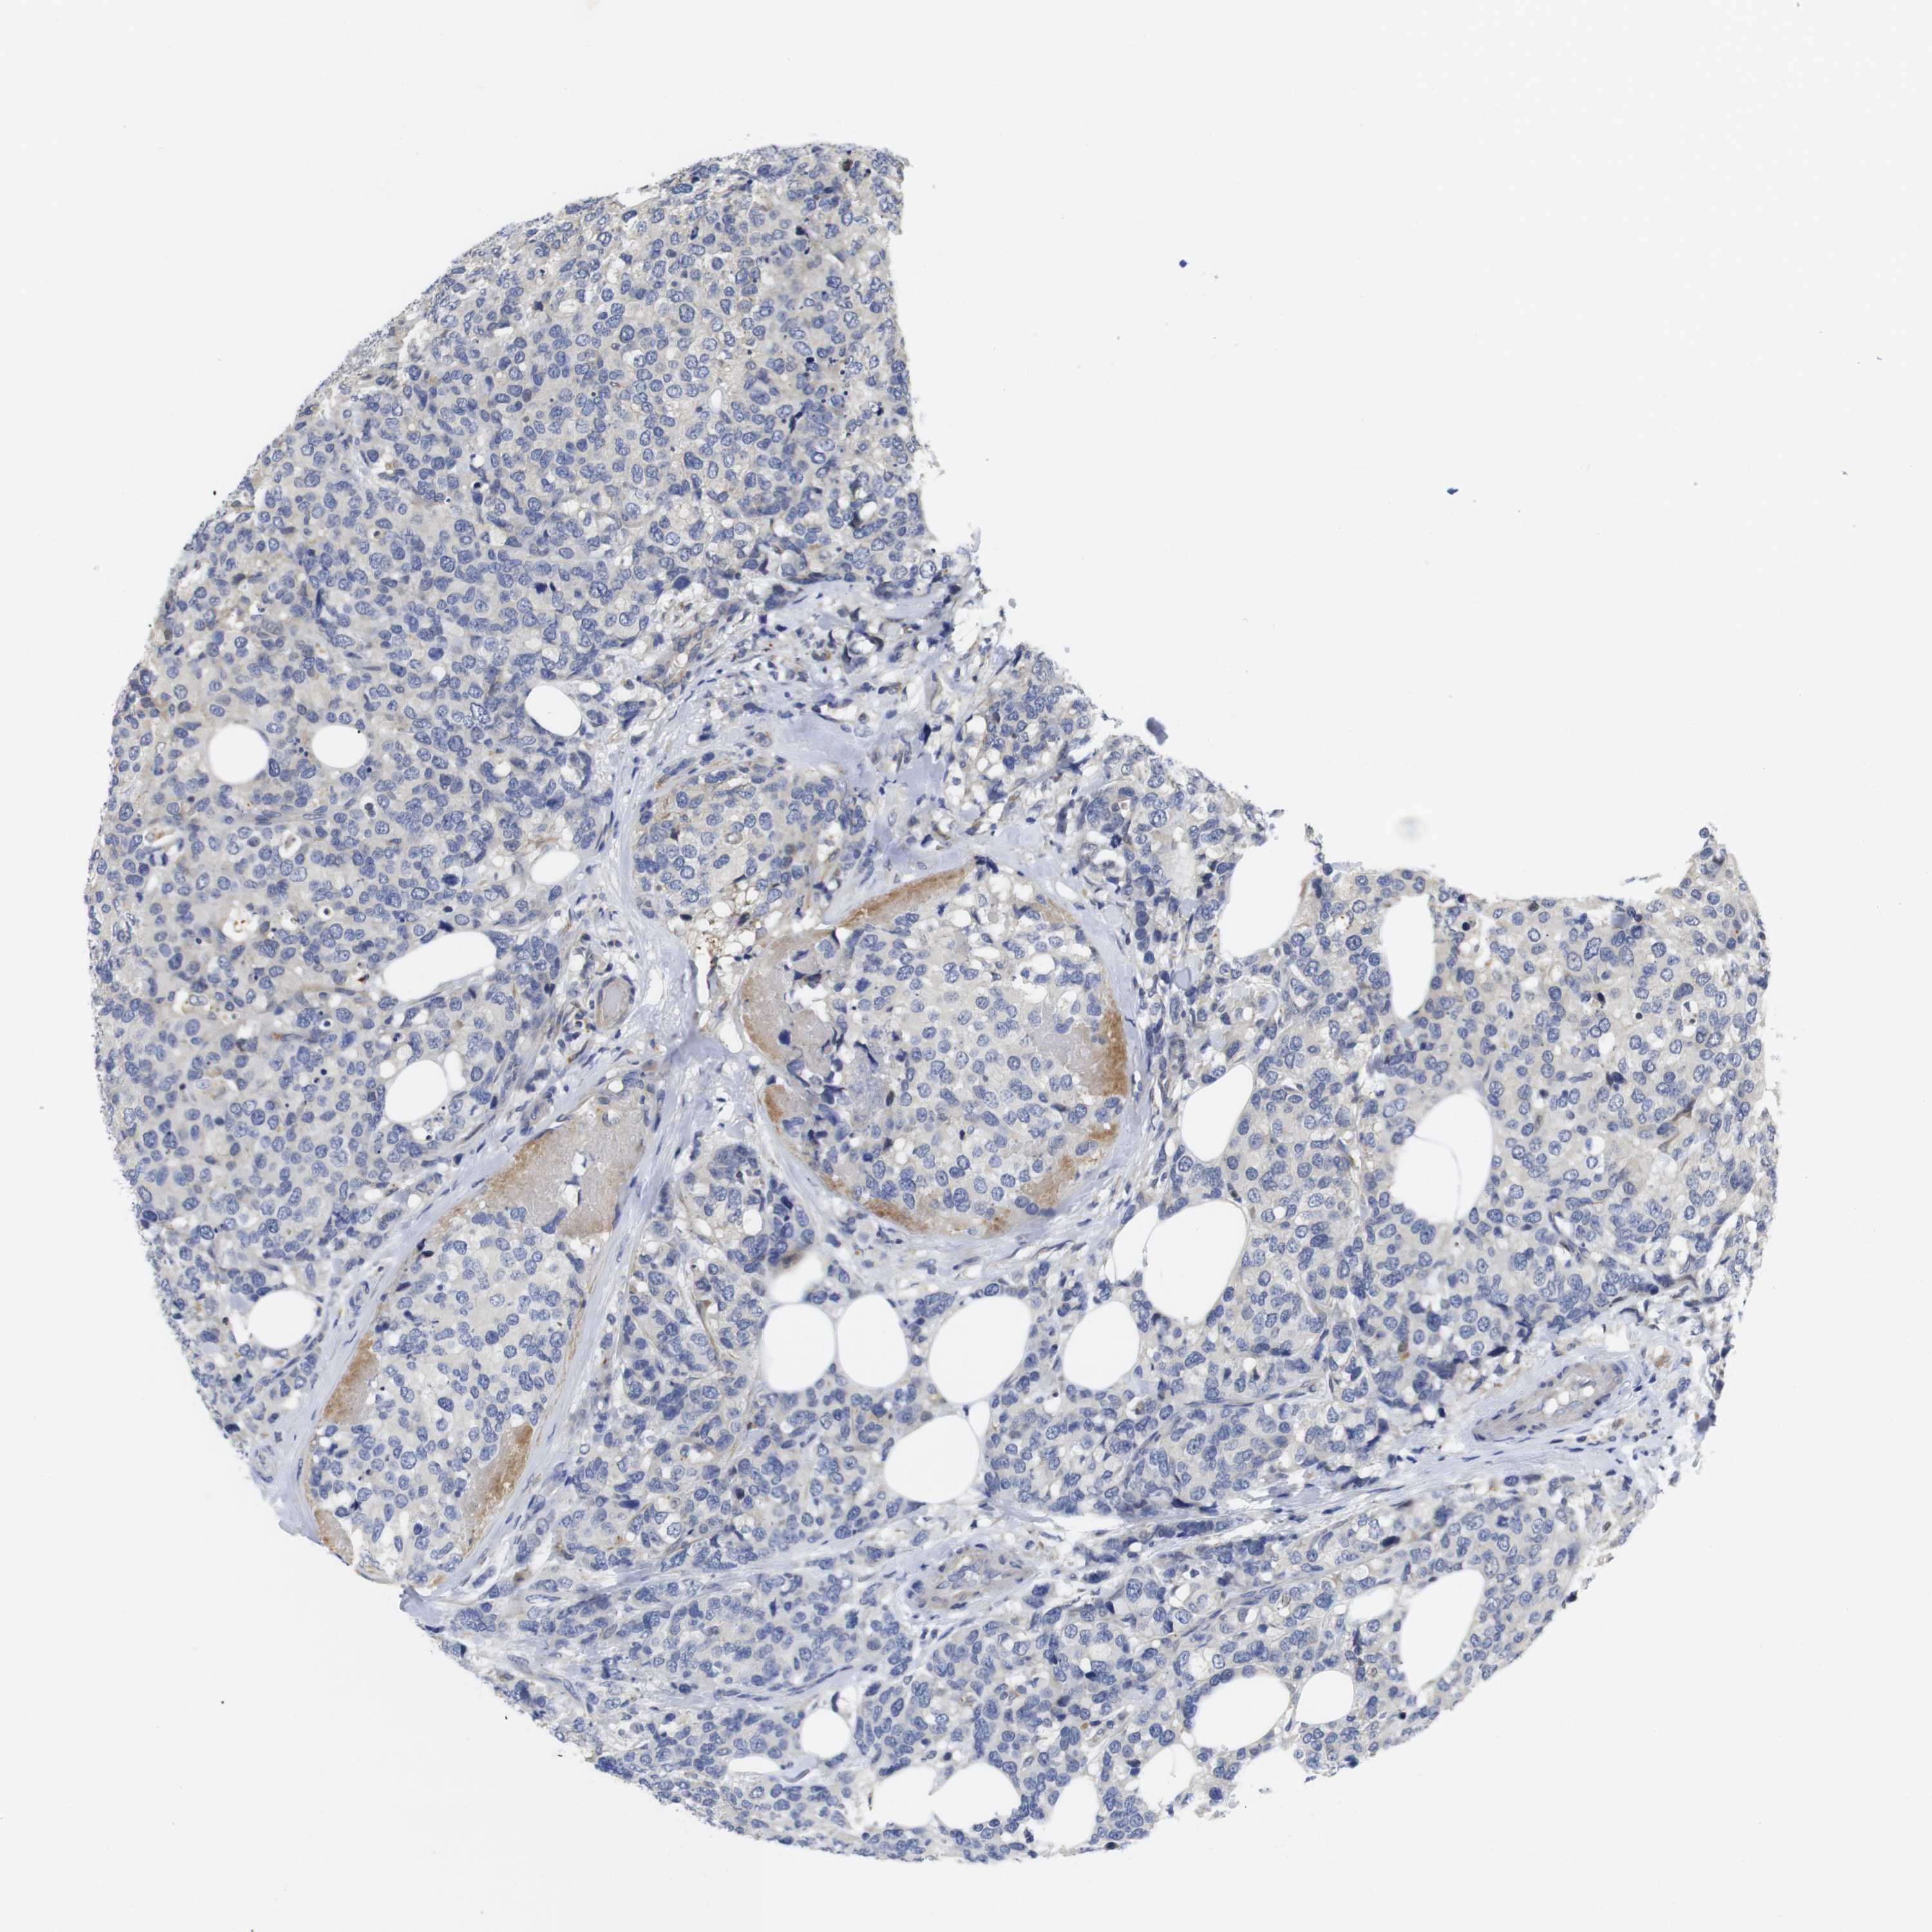

CANCER BREAST CANCER Show tissue menu

BRCA TCGA BRCA VALIDATION PROTEIN EXPRESSION